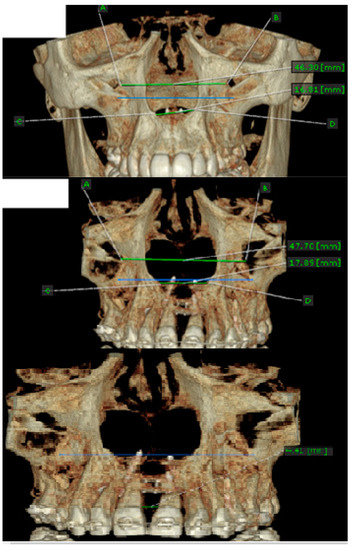

- MARPE associated with cortico-puncture therapy efficiently split the midpalatal suture in adults. The mean split at the anterior nasal spine (ANS) and posterior nasal spine (PNS) was 3.76 and 3.12 mm, respectively. The magnitude of the split at the PNS was smaller than at the ANS (by approximately 85% of the distance), showing that the opening of the midpalatal suture was almost parallel in the anteroposterior direction.

- MARPE therapy associated with cortico-puncture therapy had a positive outcome on midpalatal suture opening and maxillary advancement, but a medium molar inclination of 2.005° was also observed, suggesting that tooth movement cannot be avoided because of the anchorage of the MARPE device at the molar level.